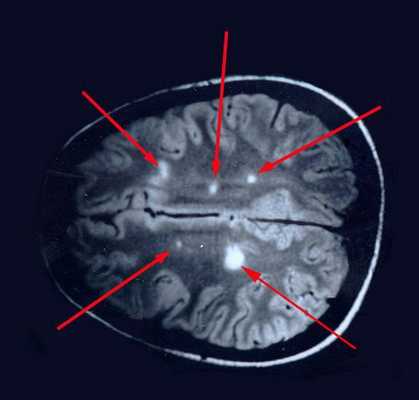

Данные МРТ

При РС на снимках магнитно-резонансной томографии могут обнаружиться очаги демиелинизации [5]. Контрастирование гадолинием помогает отличить свежие поражения от старых. В новых очагах, где еще течет воспаление, контраст сильнее накапливается, участки выглядят ярче. Наличие таких очагов говорит об активности процесса.

Исследование также помогает выявить наличие опухолей, некоторых признаков других болезней, не относящихся к РС. Но в ряде случаев МРТ может вообще не выявить никакой патологии, даже если есть аутоиммунное заболевание [7].